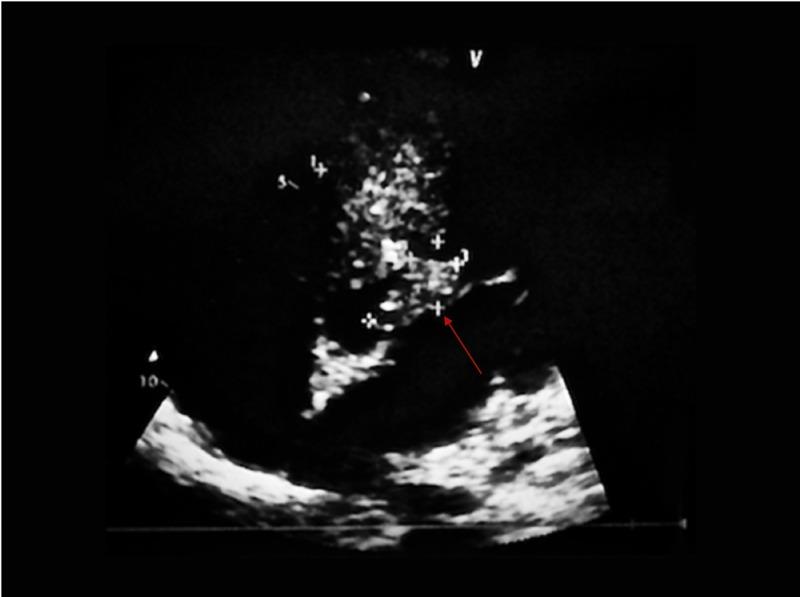

Cardiac aspergilloma is exceptionally rare with only a handful of cases reported and majority of them being in immunocompromised patients. Here, we present a case of cardiac aspergilloma involving the right and left ventricle in an immunocompetent patient that initially presented with acute limb ischemia. He was later found to have a cardiac mass with histopathological diagnosis confirming Aspergillus species. Despite aggressive medical and surgical interventions, the patient had an unfavorable outcome due to low suspicion of invasive fungal endocarditis given his immunocompetent status. Cardiac aspergilloma should remain in the differential diagnosis of immunocompetent patients as early clinical suspicion will result in early treatment and decreased mortality. Novel therapies are required to decrease mortality in the future from this fatal disease.

心脏曲霉菌瘤极为罕见,仅有少数病例报道,且大多数病例发生在免疫功能低下的患者中。在此,我们报告一例心脏曲霉菌瘤病例,该病例发生在一名免疫功能正常的患者身上,累及右心室和左心室,最初表现为急性肢体缺血。该患者后来被发现有心脏肿块,组织病理学诊断证实为曲霉菌属。尽管采取了积极的药物和手术干预措施,但由于对其免疫功能正常状态下的侵袭性真菌性心内膜炎怀疑度低,该患者预后不佳。心脏曲霉菌瘤应保留在免疫功能正常患者的鉴别诊断中,因为早期临床怀疑将导致早期治疗并降低死亡率。未来需要新的治疗方法来降低这种致命疾病的死亡率。